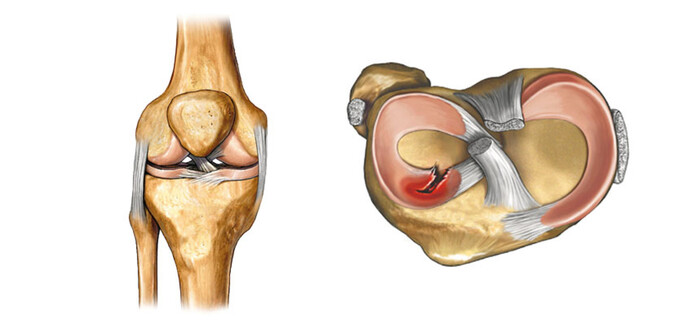

Киста Бейкера - это заполненная синовиальной жидкостью сумка в подколенной ямке между икроножной и полуперепончатой мышцами. Киста сообщается с полостью сустава через соустье, изнутри выстлана синовиальной оболочкой, снаружи - фиброзный слой.

травмы - повреждение менисков (чаще задний рог медиального мениска), разрывы передней крестообразной связки.

Один из вариантов анатомии коленного сустава, когда есть наличие соустья между капсулой сустава и икроножно-полуперепончатой сумки в подколенной ямке. В соустье есть клапан, который позволяет жидкости из сустава переходить в сумку.

Или из-за повреждения мениска, который начинает играть роль клапана.

Другой вариант - киста Бейкера, это грыжевой выпячивание синовиальной оболочки сустава в наиболее уязвимом месте.